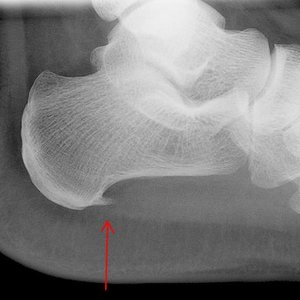

Ostroga piętowa jest schorzeniem, którego nie można bagatelizować. Wynika to przede wszystkim z bólu, jaki powoduje podczas chodzenia, leżenia, siedzenia. Nawet jeśli na początku jest to tylko niewielki ból, z czasem stanie się silniejszy. Z tego powodu już pierwsze objawy powinny sprowokować do udania się do lekarza w celu prawidłowego zdiagnozowania problemu oraz rozpoczęcia leczenia.

Schorzenie jest spowodowane zwyrodnieniem pomiędzy kością pięty a rozcięgnem mięśniowym, który odpowiada za swobodne rozluźnianie i napinanie się tego rejonu ciała podczas chodzenia. Zapalenie tego obszaru powoduje ból odczuwany przede wszystkim w pięcie oraz w podeszwie pięty. Cierpią na nie przede wszystkim osoby starsze, których stopy ulegają deformacji, oraz osoby, które uprawiają niektóre dziedziny sportu, np. tenis, bieganie. Nie jest regułą, że sportowiec będzie cierpiał na tę przypadłość, jednak istnieje zwiększone ryzyko jej pojawienia się.